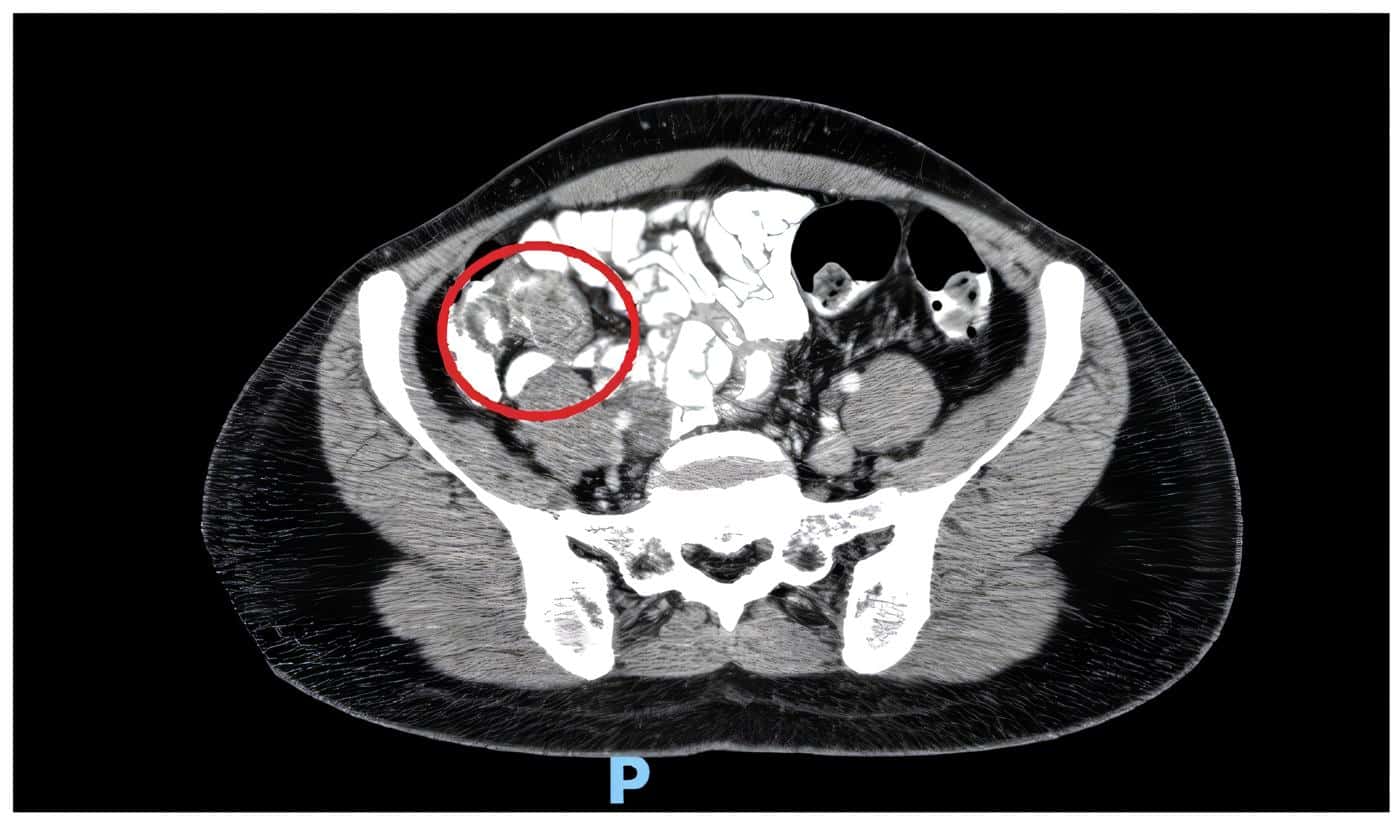

La ecografía transvaginal informó la presencia de ovarios de aspecto poliquístico. El control de las pruebas de laboratorio no mostró elevación de reactantes inflamatorios pero la paciente persistía sintomática, por lo que se realizó una tomografía computarizada de abdomen, en la que se observaron intususcepción del apéndice sobre el ciego y estriación de la grasa pericecal, así como adenomegalias de la cadena ilíaca derecha de aspecto reactivo (figuras 1 y 2).

Figura 2. Tomografía computarizada de abdomen, corte axial donde se observa el signo de la doble diana, inflamación de la grasa pericecal, y sin paso del medio de contraste al ciego, en el sitio de la invaginación. Fuente: Elaboración propia de los autores.